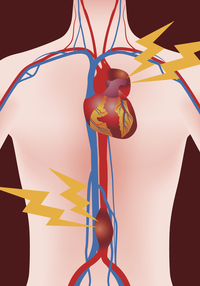

Treatment for an unruptured brain aneurysm may be appropriate in some cases and may prevent a rupture in the future. This type of hemorrhagic stroke is called a subarachnoid hemorrhage. Many have no symptoms and are not dangerous. A sudden, severe headache is the key symptom of a ruptured aneurysm. An aneurysm occurs when an artery's wall weakens and causes an abnormally large bulge. Blurred or double vision 5. Common signs and symptoms of a ruptured aneurysm include: A number of factors can contribute to weakness in an artery wall and increase the risk of a brain aneurysm or aneurysm rupture.

Sudden, extremely severe headache 2. In some cases, an aneurysm may leak a slight amount of blood. If the aneurysm ruptures, you might feel sick to your stomach, or suddenly develop an intense pain in your back or abdomen. However, a larger unruptured aneurysm may press on brain tissues and nerves, possibly causing: Treatment for an unruptured brain aneurysm may be appropriate in some cases and may prevent a rupture in the future. 'an aneurysm is a swelling in part of an artery caused by damage to, or weakness of, a blood vessel wall.'. Although an aneurysm can occur in any part of. Blurred or double vision 5. See full list on mayoclinic.org An unruptured brain aneurysm may produce no symptoms, particularly if it's small. See full list on mayoclinic.org A number of factors can contribute to weakness in an artery wall and increase the risk of a brain aneurysm or aneurysm rupture. Aneurysms there are serious, while those in other areas, such as your leg, can be less hazardous.

Arteries are blood vessels that carry blood from your heart to your organs. Change in vision or double vision 4. A brain aneurysm can leak or rupture, causing bleeding into the brain (hemorrhagic stroke). A number of factors can contribute to weakness in an artery wall and increase the risk of a brain aneurysm or aneurysm rupture. An unruptured brain aneurysm may produce no symptoms, particularly if it's small.

An excessive localized enlargement of an artery caused by a weakening of the artery wall. This type of hemorrhagic stroke is called a subarachnoid hemorrhage. Sudden, extremely severe headache 2. A brain aneurysm can leak or rupture, causing bleeding into the brain (hemorrhagic stroke). Brain aneurysms are more common in adults than in children and more common in women than in men. Talk with your caregiver to ensure you understand the best options for your specific needs. If the aneurysm ruptures, you might feel sick to your stomach, or suddenly develop an intense pain in your back or abdomen. Complications that can develop after the rupture of an aneurysm include: It also increases pressure inside the skull. Most brain aneurysms, however, don't rupture, create health problems or cause symptoms. A number of factors can contribute to weakness in an artery wall and increase the risk of a brain aneurysm or aneurysm rupture. Sudden, extremely severe headache a more severe rupture often follows leaking. See full list on mayoclinic.org

When a brain aneurysm ruptures, the bleeding usually lasts only a few seconds. An excessive localized enlargement of an artery caused by a weakening of the artery wall. Common signs and symptoms of a ruptured aneurysm include: It often looks like a berry hanging on a stem. This headache is often described as the worst headache ever experienced.